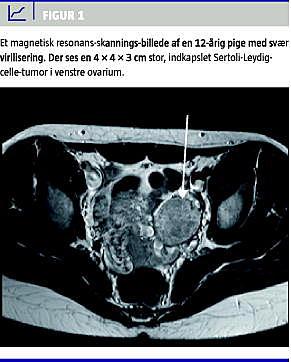

En ultralydundersøgelse af abdomen og genitalia interna viste intet abnormt, men en magnetisk resonans-skanning af abdomen viste en solid tumor i venstre ovarium (Figur 1 ).

Ved unilateral ooforektomi fjernede man en 4 × 4 × 3 cm stor Sertoli-Leydig-celle-tumor. Da tumoren var indkapslet uden regionale lymfeknude- og/eller fjernmetastaser (FIGO-stadie T1a), undgik man adjuverende behandling.